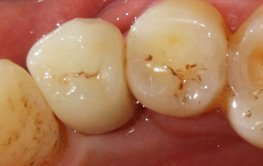

患者:***      男        43岁

病历号:16060809

初诊时间:2016年6月8日

结束时间:2017年3月25日

主诉:要求种植。

现病史:一月前,患者左下后牙松动脱落,就诊。

既往史:体健,否认传染病史及药物过敏史。

检查:颌面部未见异常,口内查:34缺失,牙槽骨低平,牙龈无红肿。

CBCT:34颊侧骨缺损。

诊断:下牙列缺损。

治疗方案:34植骨+美格真种植修复。

备洞

治疗过程:34必兰局麻下,切开翻瓣,在生理盐水冷却下,先锋钻,扩孔钻逐级备洞,植入美格真4.0*11.5mm种植体一枚,颊侧植骨+GBR,严密缝合。

1.jpg